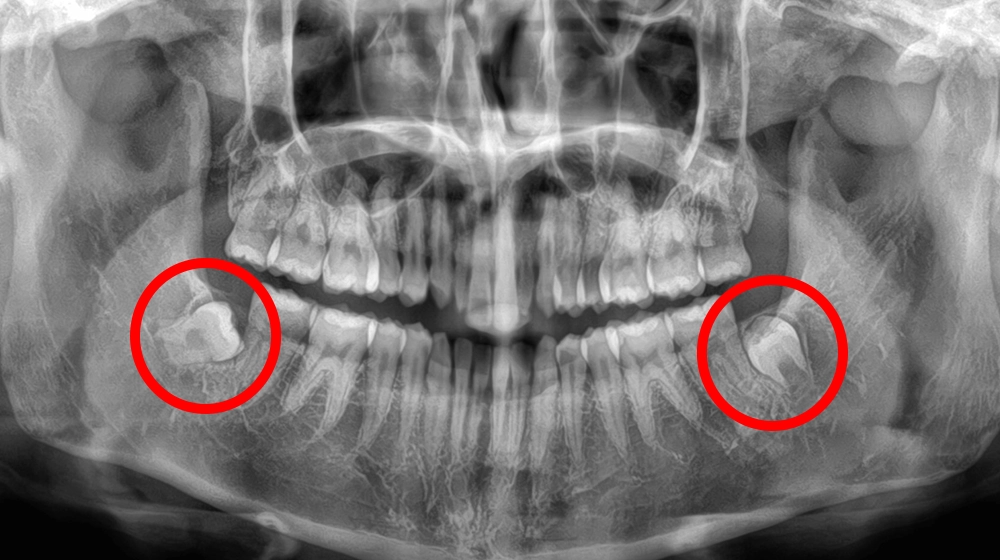

まっすぐ生えている

親知らず抜歯

まっすぐ生えている親知らずイメージ

費用(1本) 約1,500〜2,000円

抜歯時間 約1〜5分